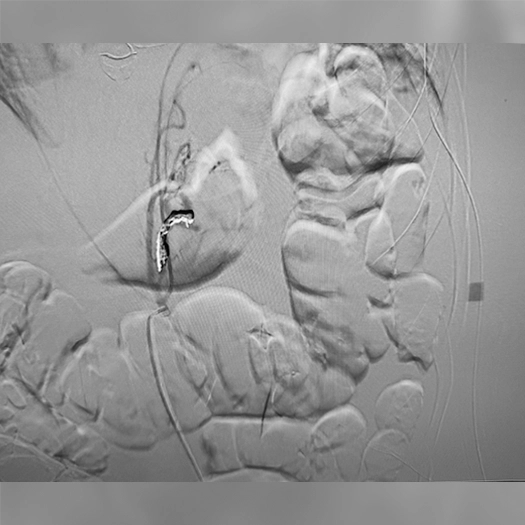

Zoomed in view of Ruby XL Detail

Coils Used: 8mm x 70cm POD XL, 5mm x 30cm POD XL

Catheter: 4F Glide Cath